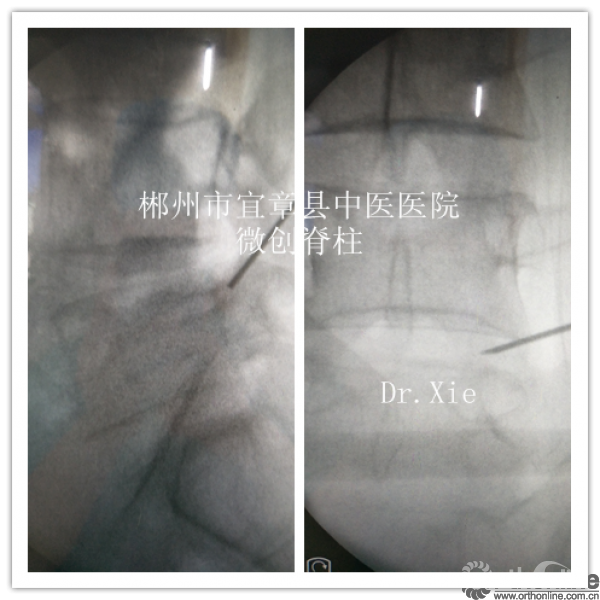

术前体表做好标记

穿刺起点:上关节突基底部

终点:下位椎体椎弓根上部

成型部位:关节突基底部及椎弓根上缘,对于向下游离及神经根管狭窄的患者尤为适合。

置管及成型时候正侧位情况